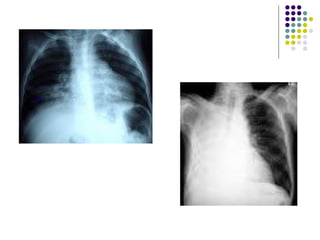

COMPLICACIONES QUIRURGICAS DERRAME PLEURAL:- Es el acúmulo anormal de un exceso de líquido en la cavidad torácica que resulta del desequilibrio entre la formación del líquido pleural y su remoción ETIOLOGIA:- 1.-Enfermedades de la pleura o los pulmones. 2.-Alteraciones extrapulmonares:- **Cardíacas (ICC),Renales (síndrome nefrótico), hepáticas  (cirrosis con ascitis), pancreáticas (pancreatitis). **Enfermedades sistémicas (LES, artritis reumatoidea), o  por reacción a drogas (nitrofurantoina). **Neoplásico.

COMPLICACIONES QUIRURGICAS MANIFESTACIONES CLINICAS:- 1.- Dolor pleurítico. 2.- Disnea. 3.- Taquipnea. 4.- Disminución del murmullo vesicular y  frémito vocal, de la expansibilidad  torácica, matidez. TRATAMIENTO:- 1.- Drenaje (Toracocentesis).

COMPLICACIONES QUIRURGICAS DERRAMEPLEURAL:- Es el acúmulo anormal de un exceso de líquido en la cavidad torácica que resulta del desequilibrio entre la formación del líquido pleural y su remoción ETIOLOGIA:- 1.-Enfermedades de la pleura o los pulmones. 2.-Alteraciones extrapulmonares:- **Cardíacas (ICC),Renales (síndrome nefrótico), hepáticas (cirrosis con ascitis), pancreáticas (pancreatitis). **Enfermedades sistémicas (LES, artritis reumatoidea), o por reacción a drogas (nitrofurantoina). **Neoplásico.

COMPLICACIONES QUIRURGICAS MANIFESTACIONESCLINICAS:- 1.- Dolor pleurítico. 2.- Disnea. 3.- Taquipnea. 4.- Disminución del murmullo vesicular y frémito vocal, de la expansibilidad torácica, matidez. TRATAMIENTO:- 1.- Drenaje (Toracocentesis).